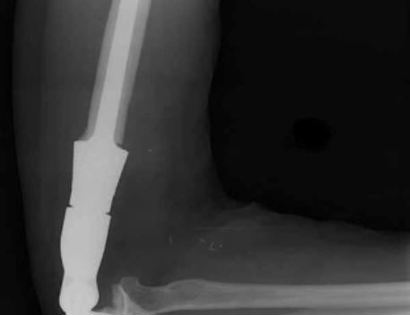

This is an X-ray image of the arm with the prosthesis.